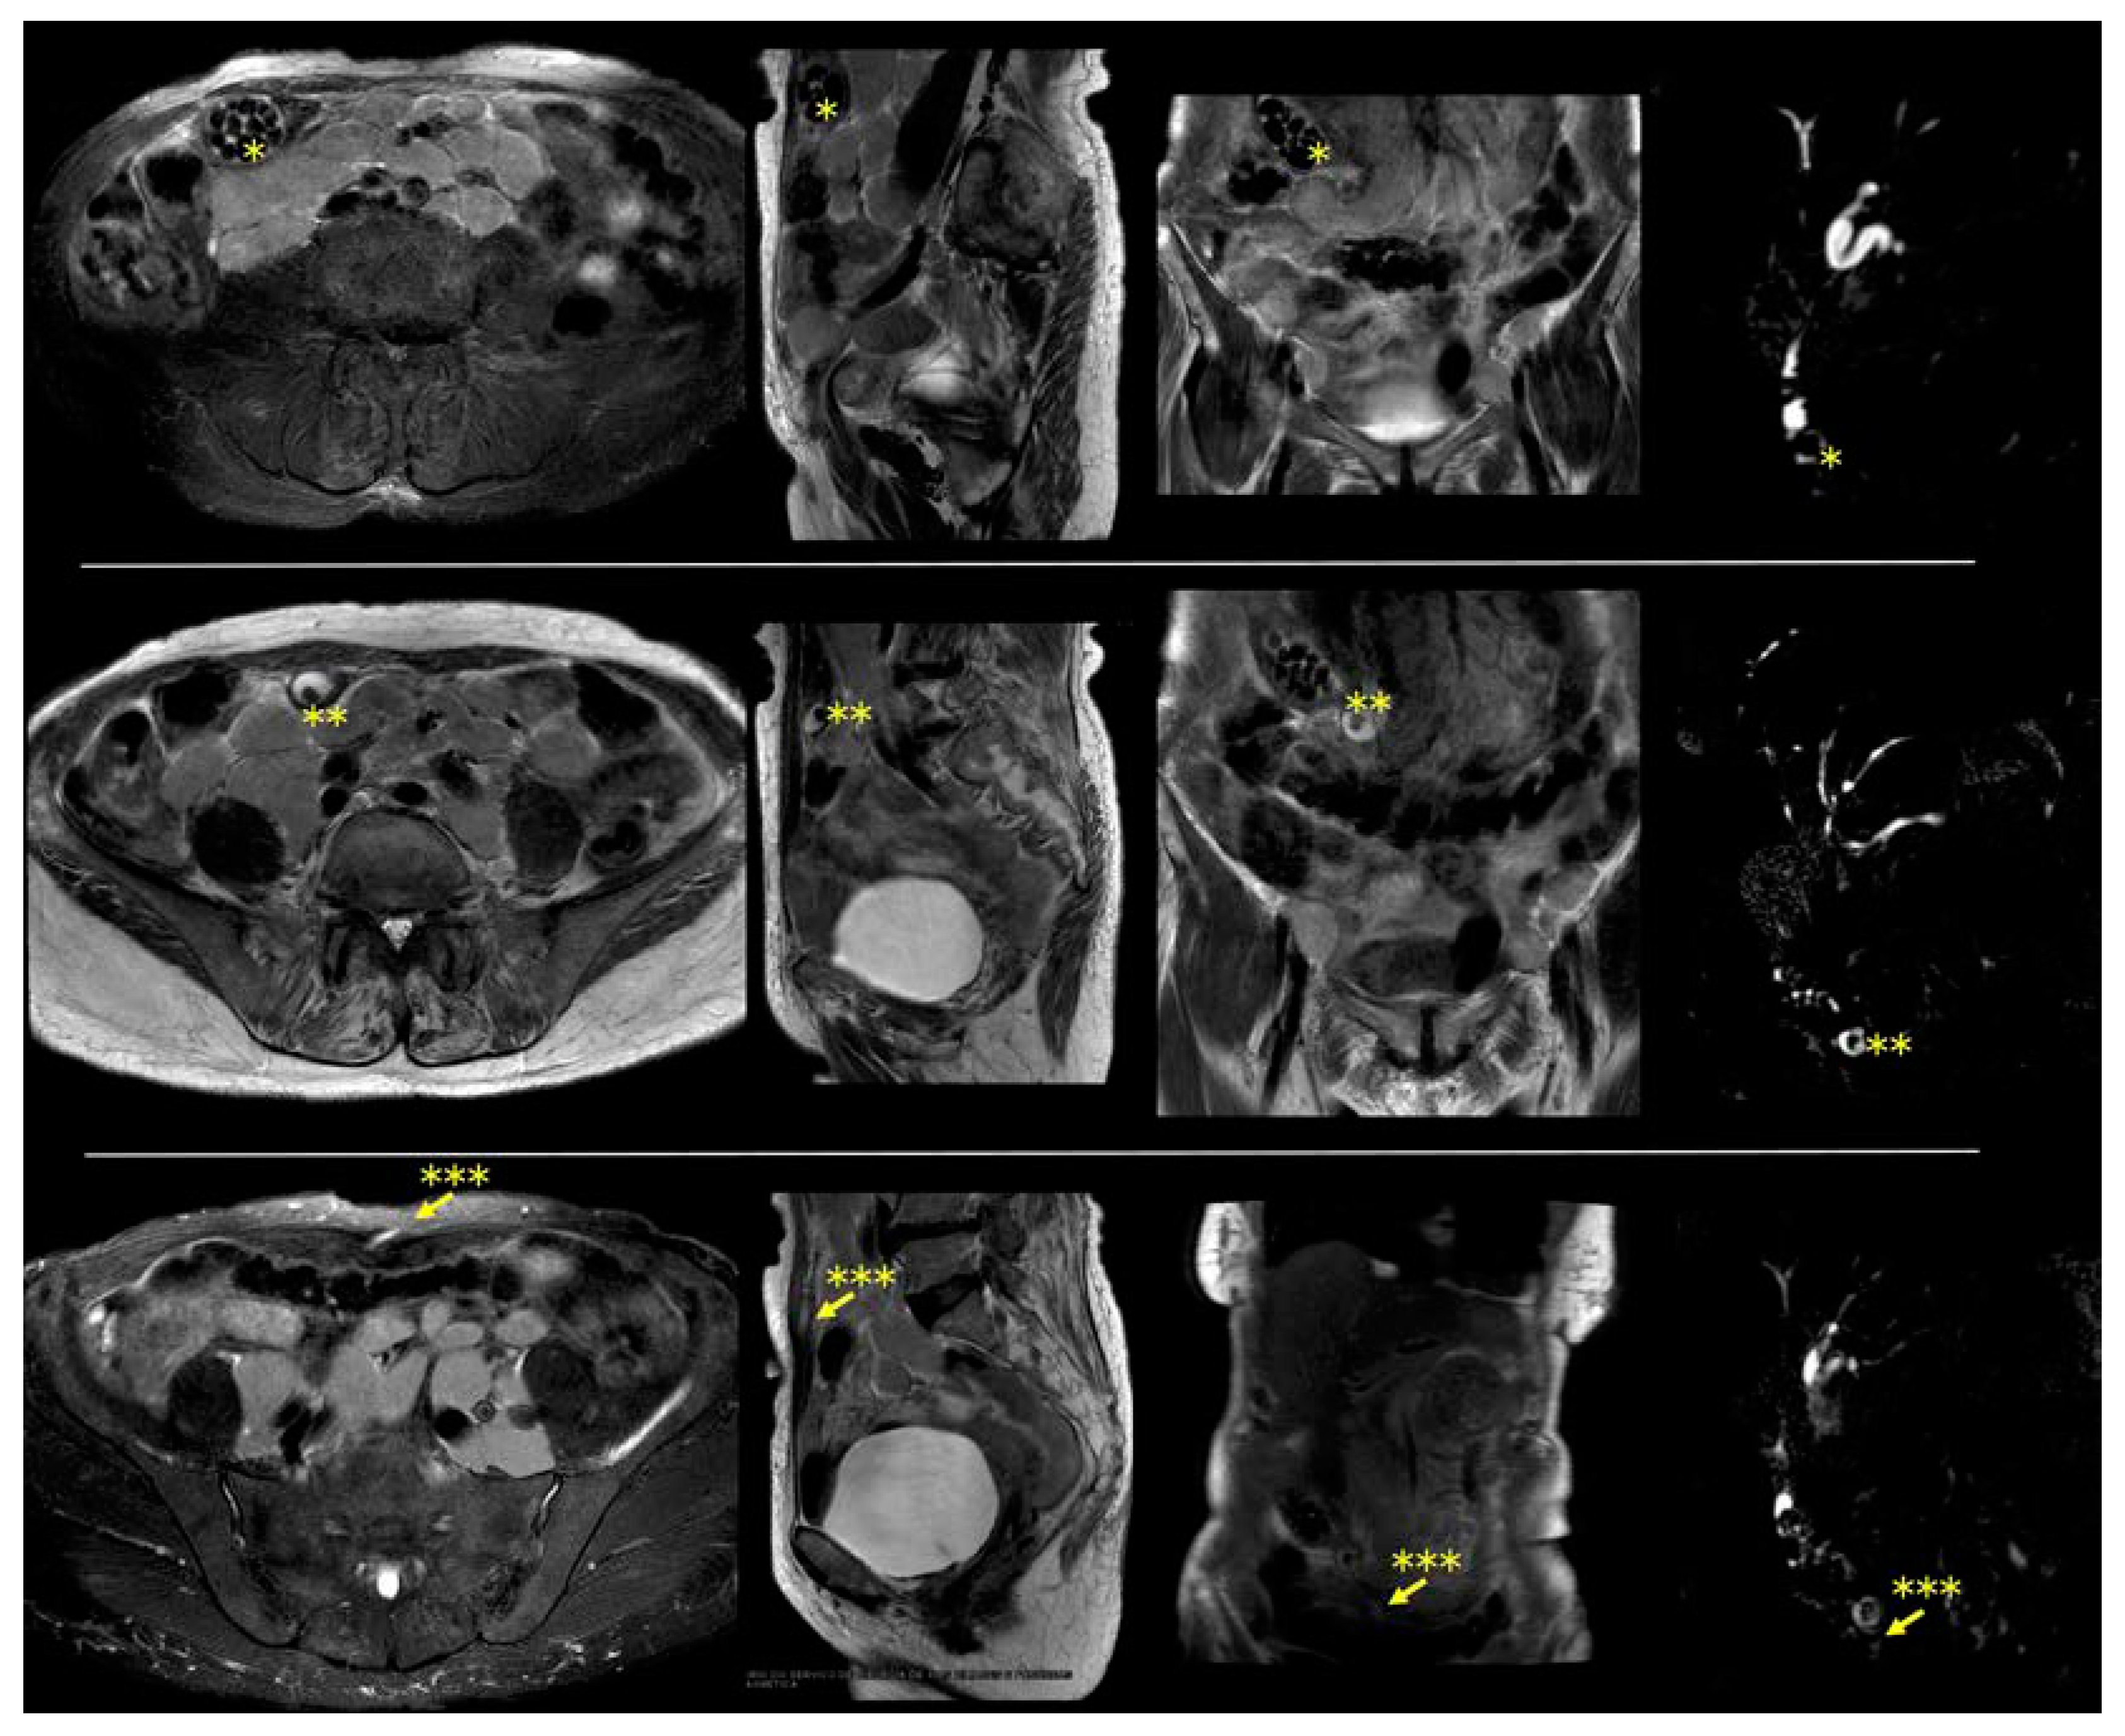

Figure 1. Magnetic resonance imaging shows a caudally displaced gallbladder with numerous stones and with cholecystocutaneous fistula. Left to right: axial, sagittal, coronal, and cholangiography. * Displaced gallbladder; ** stone inside the fistula; *** cholecystocutaneous fistula (indicated by arrow).

Supplementary Video S1. Magnetic resonance imaging showing a cholecystocutaneous fistula. An 88-year-old indigenous woman from the Brazilian countryside was referred for surgical evaluation due to a small lump in the anterior abdominal wall, with the main diagnostic hypothesis being a sebaceous cyst. This lump emerged years ago, and it used to become painful and inflamed on some days. Additionally, the patient reported that, occasionally, some stones emerged from this lump. The patient had no comorbidities. However, the patient had a history of several episodes of abdominal pain, for which she went to numerous different hospitals in the countryside, was always treated with analgesics, and then discharged. She also reported occasional fever. The intensity of symptoms had decreased in the last few years. She had never undergone any imaging test. The results of serum tests were unremarkable. After surgical team evaluation, the patient underwent magnetic resonance, which showed a displaced gallbladder with diffusely thickened walls, multiple stones, and a fistulous tract extending from the gallbladder to the skin of the anterior abdominal wall. In addition, multiple confluent retroperitoneal enlarged lymph nodes were found in this exam. The patient was referred for hematological consultation to investigate retroperitoneal lymph node enlargement. The patient died of pneumonia some months later without treating the cholecystocutaneous fistula. The cholecystocutaneous fistula usually affects elderly women, with an average age of 72 years, with poor socioeconomic conditions and poor access to the health system [1,2]. Although the definitive treatment for this condition is a cholecystectomy with fistula excision, high-risk patients may experience treatment delays [2,3]. Vulnerable patients face inefficient and slow healthcare, and the time required for diagnosis and treatment planning can extend over years. Consequently, the patient remained untreated, enduring symptoms and an impaired quality of life. This case underscores the significant challenges faced by patients in regions with limited healthcare access, highlighting the impact of delayed diagnosis and inadequate management on patient outcomes (Figure 1).